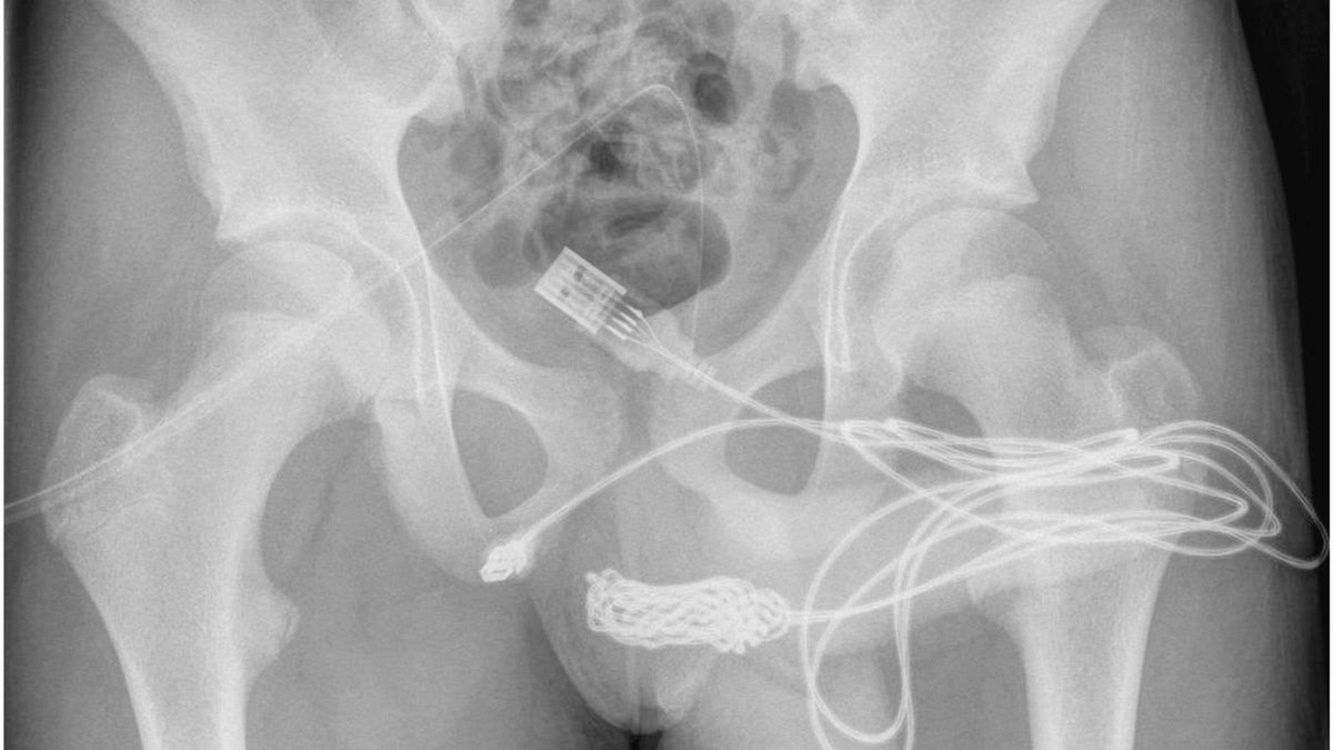

Lekarze byli zmuszeni przeprowadzić operację, by wydostać kabel z ciała

Lekarze byli zmuszeni przeprowadzić operację, by wydostać kabel z ciała © Twitter

Przez ilość powstałych supełków na kablu, lekarze również nie mogli go usunąć. By wydostać przewód z wnętrza cewki moczowej, chłopak musiał przejść operację. Finalnie oba końce przewodu wyciągnięto przez zewnętrzne ujście cewki moczowej.

Chłopak został wypisany ze szpitala, a dwa tygodnie później usunięto cewniki. Lekarze nie są jednak w stanie stwierdzić, jakie będą długotrwałe skutki takiej zabawy. 15-latek będzie więc pozostawał pod obserwacją.